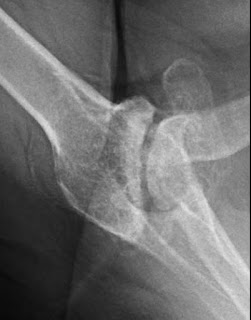

With some conservative sculpting of her glenoid, we were able to establish a secure, appropriately contoured glenoid bone surface onto which a standard glenoid component was secured. Sufficient glenoid bone stock remains for a reverse total shoulder should this reconstruction fail in the future.

Her postoperative x-rays are shown below.